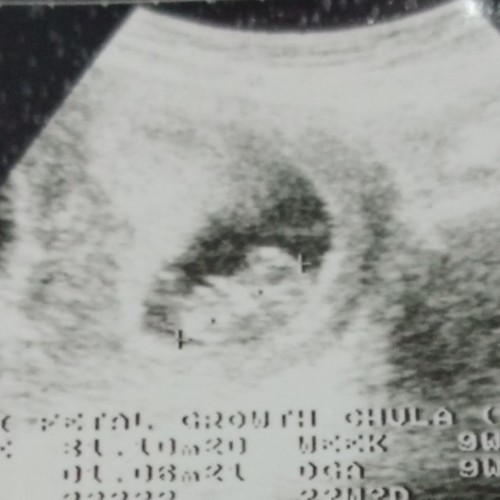

8w+6d ตอนนี้27w+5d